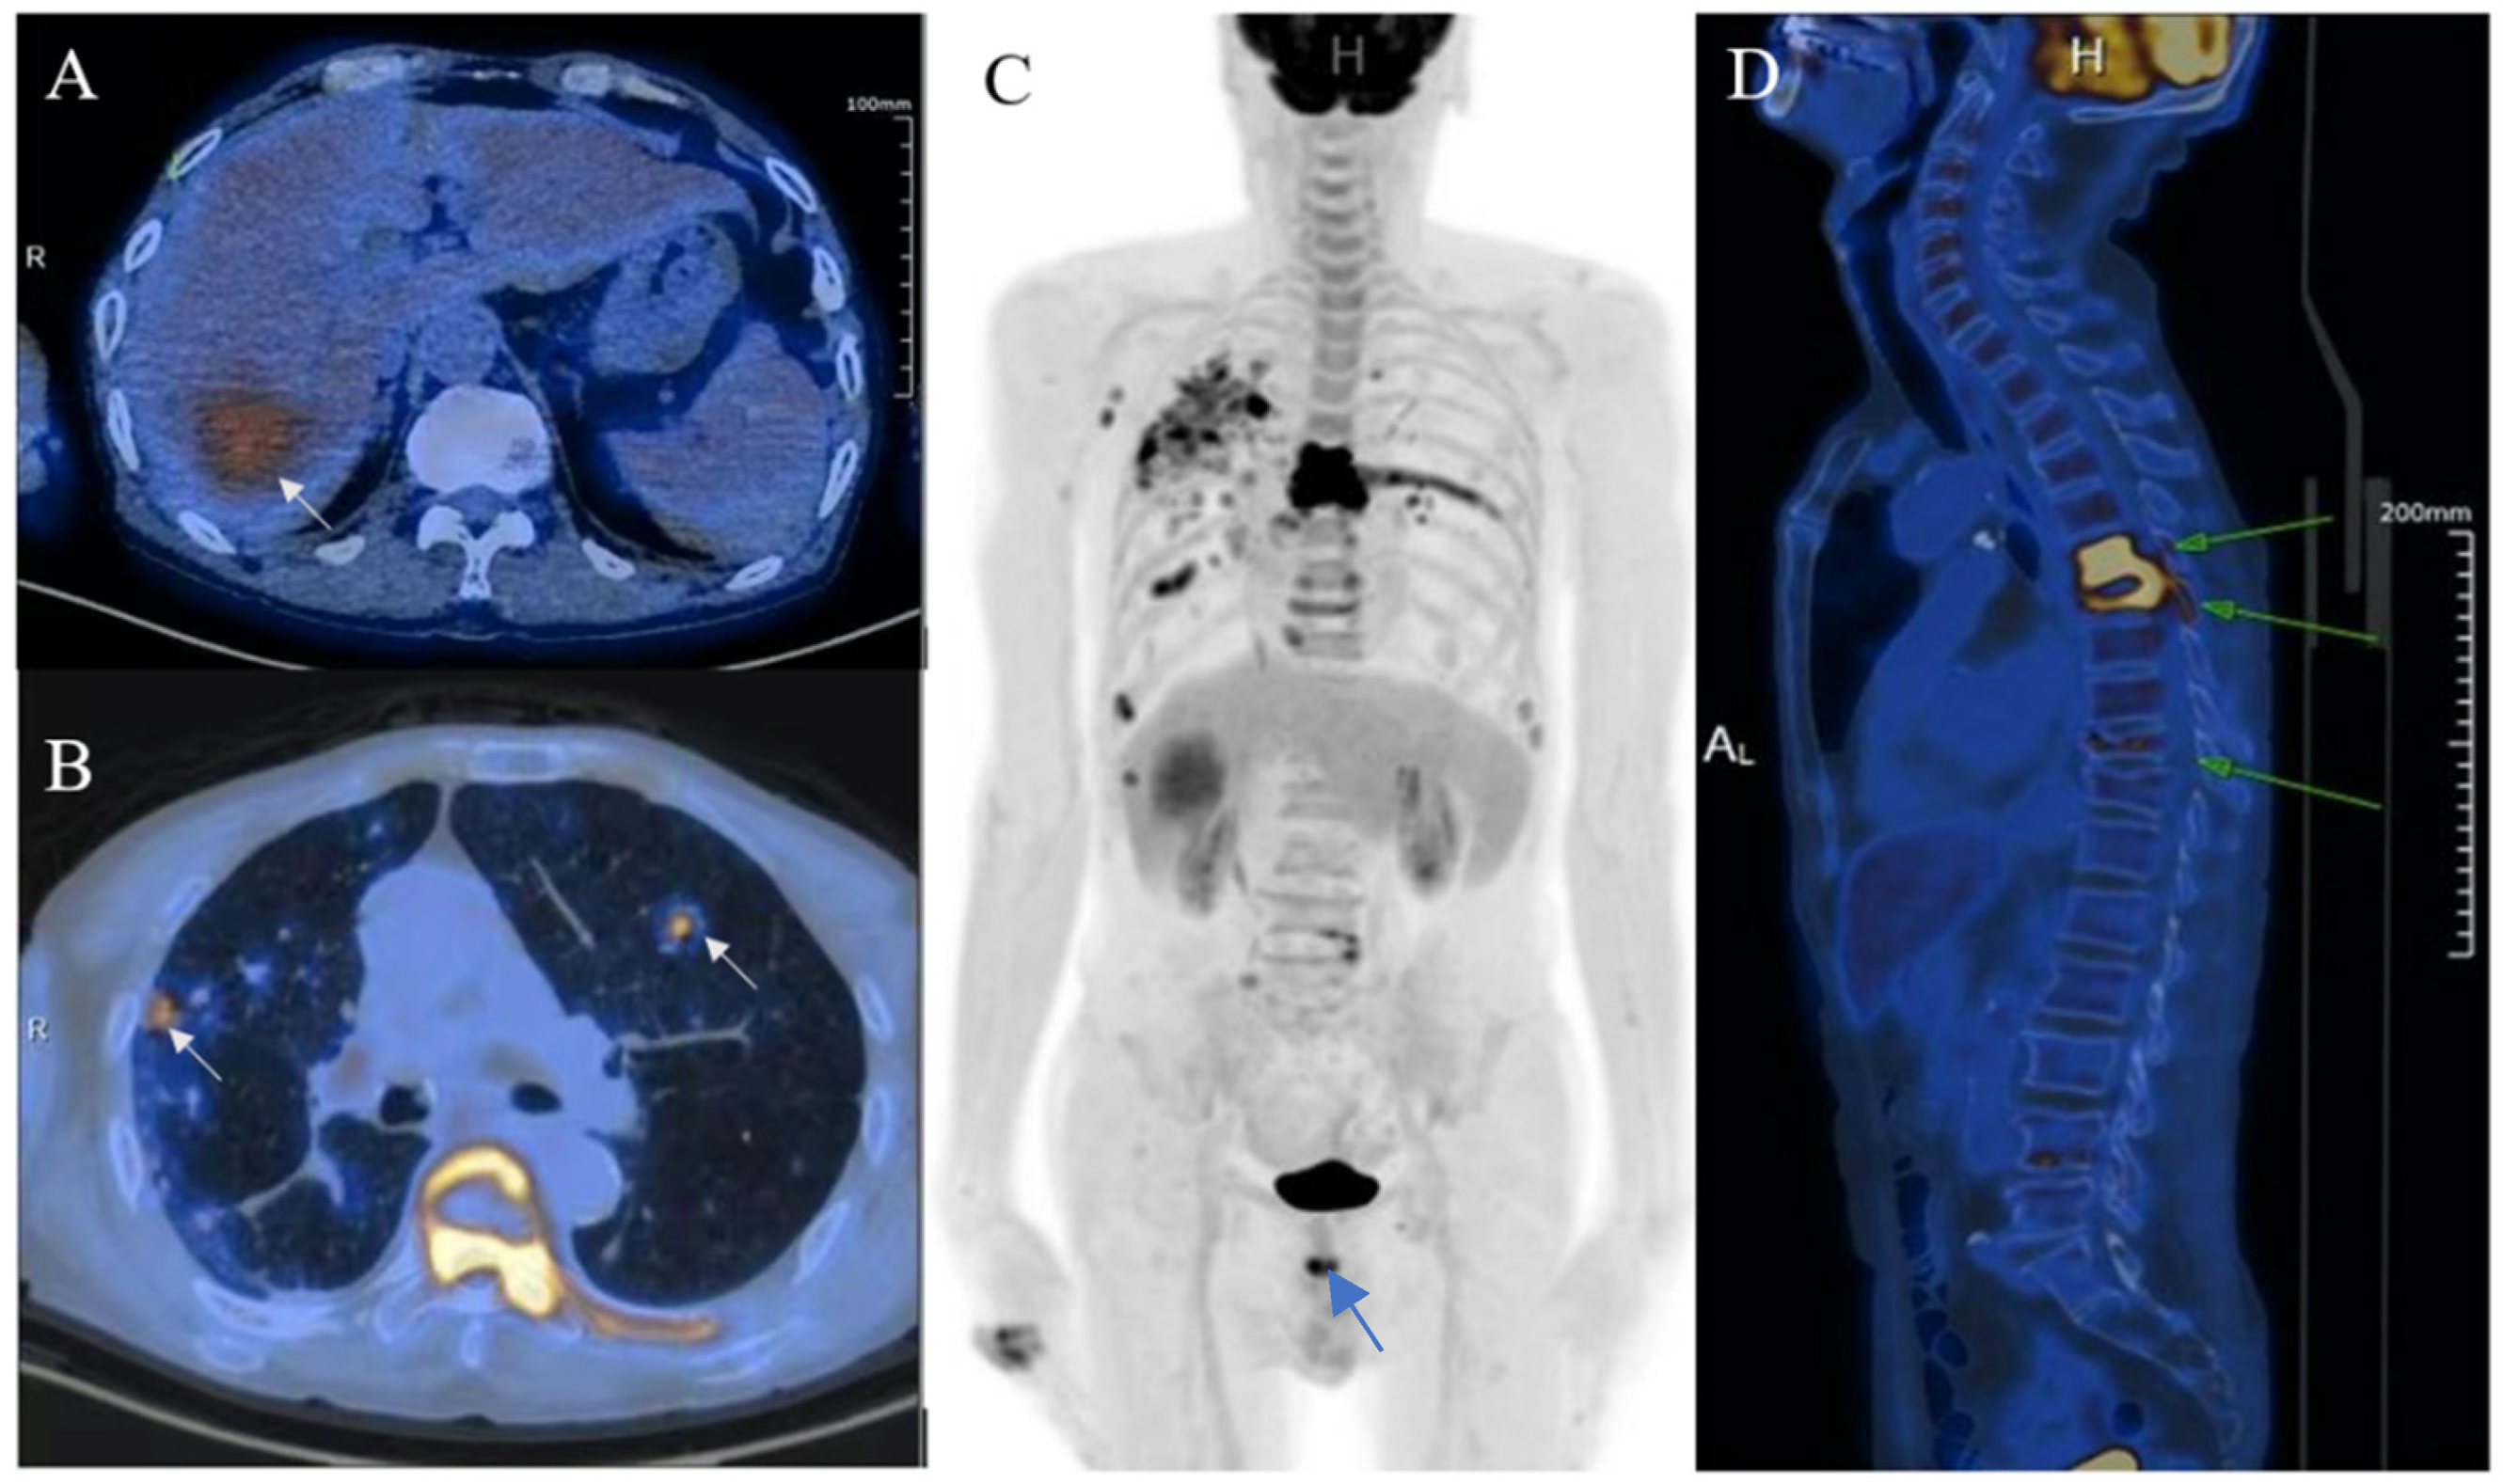

Ultrasound-guided percutaneous coarse needle biopsy (US-CNB) was carried out to acquire pathological diagnosis (A). The biopsy site and positioning were chosen after careful ultrasound examination and a spring-loaded 18-gauge core biopsy needle was used (MAXCORE®, Bard Medical Technologies Inc., Murray Hill, NJ, USA). Three cores of specimens were obtained and then sent for pathologic evaluation. Hematoxylin and eosin staining showed that the tumor was comprised of pigmented fusiform cells on microscopy scan ((B), 200×, arrow). Immunohistochemical staining demonstrated that the tumor cells were strongly and extensively stained with MITF and S-100, but it was negative for BRAF V600E. Consequently, the liver lesion was confirmed as metastatic melanoma. Of note, there was no history of cutaneous melanoma, and no primary tumor was revealed by systemic skin examination. In addition, a standard comprehensive examination for mucosal, ocular, and other occult sources did not reveal a definitive primary tumor. Due to the fever and pulmonary tuberculosis, the patient may not tolerate the side effects of systemic therapy. Finally, he refused systemic therapy and died from tumor progression seven months after the initial diagnosis. The incidence of melanoma increased rapidly in the United States as well as in Asian countries during the past few decades [2]. Over 90% of melanoma patients suffer from liver metastasis during the course of their disease, which generally implies poor prognosis [3]. Obtaining accurate diagnosis and clinical stage of the melanoma is important for individualized therapy and surveillance. However, isolated hepatic metastatic melanoma is difficult to recognize by imaging methods especially for those without a determined origin. In this case, the hepatic lesion was mistaken as hepatapostema using CEUS, whereas it was misdiagnosed as HCC using CEMRI. Clinically, the CEUS features of hepatapostema varies between different stages, presenting as temporal sub-segmental hyperenhancement without necrosis during the early stage, which is indistinguishable from solid tumors [4]. It is worth noting that the characteristic signal of melanoma is hyperintense on T1-weighted imaging due to the paramagnetism of melanin. Although rare, the imaging features of metastatic melanoma are varied, and may present as cystic, solid-cystic or solid nodule [5,6]. Thus, once it is detected, it’s difficult to recognize immediately. The treatment of malignant melanoma depends on the age, clinical staging, general condition, and personal preferences of the patient [7]. When 18F-FDG-PET/CT suggested that the tumor was in stage IV, histological examination was essential to determine the individual treatment schedule. US-CNB has been the procedure of choice in tissue diagnosis for its availability, high accuracy, and safety [8]. As such, an increasing number of biopsies has been performed in our center during the past few years. Whenever inconclusive imaging findings persist, US-CNB is performed by an experienced operator. The obtained tissue specimen is used for precise definition of specific biomarkers. In brief, the isolated hepatic malignant melanoma with undetermined origin is a rare condition and difficult to distinguish from other tumors through noninvasive imaging methods. CEUS and CEMRI play a fundamental role in the diagnosis of hepatic melanoma, and PET-CT is useful in clinical staging. For controversial results, US-CNB is essential to establish the pathological diagnosis.